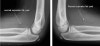

3) Supinator fat pad sign

Supinator fat pad can be raised or obliterated as a result of bony injury, particularly to the radial neck.

It is one of those unreliable soft tissue signs, but is useful as a guide to potential bony injury.

- AP view

Medial or lateral epicondyle에 손상이 있는 경우 주변 연부조직이 부을 수 있습니다.